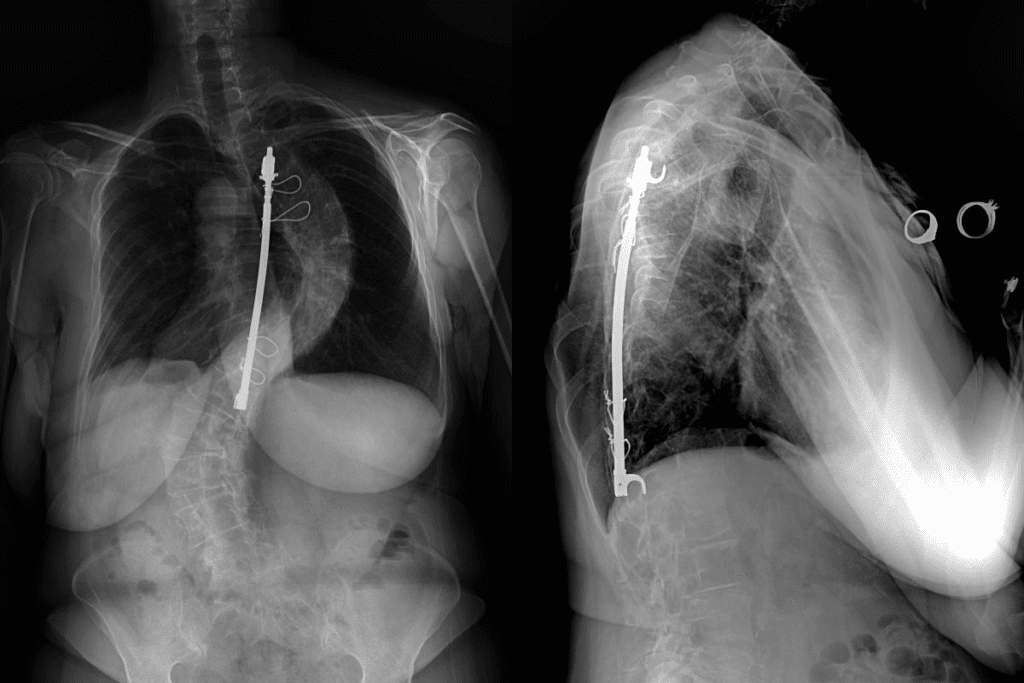

Imaging Studies for Adult Scoliosis

Imaging tests are key for diagnosing and figuring out how severe scoliosis is. The main tests are:

- X-rays: To see how curved your spine is and its alignment.

- CT scans: For detailed images of your spine, including vertebrae and discs.

- MRI scans: To see soft tissues like nerves and discs and spot any problems.